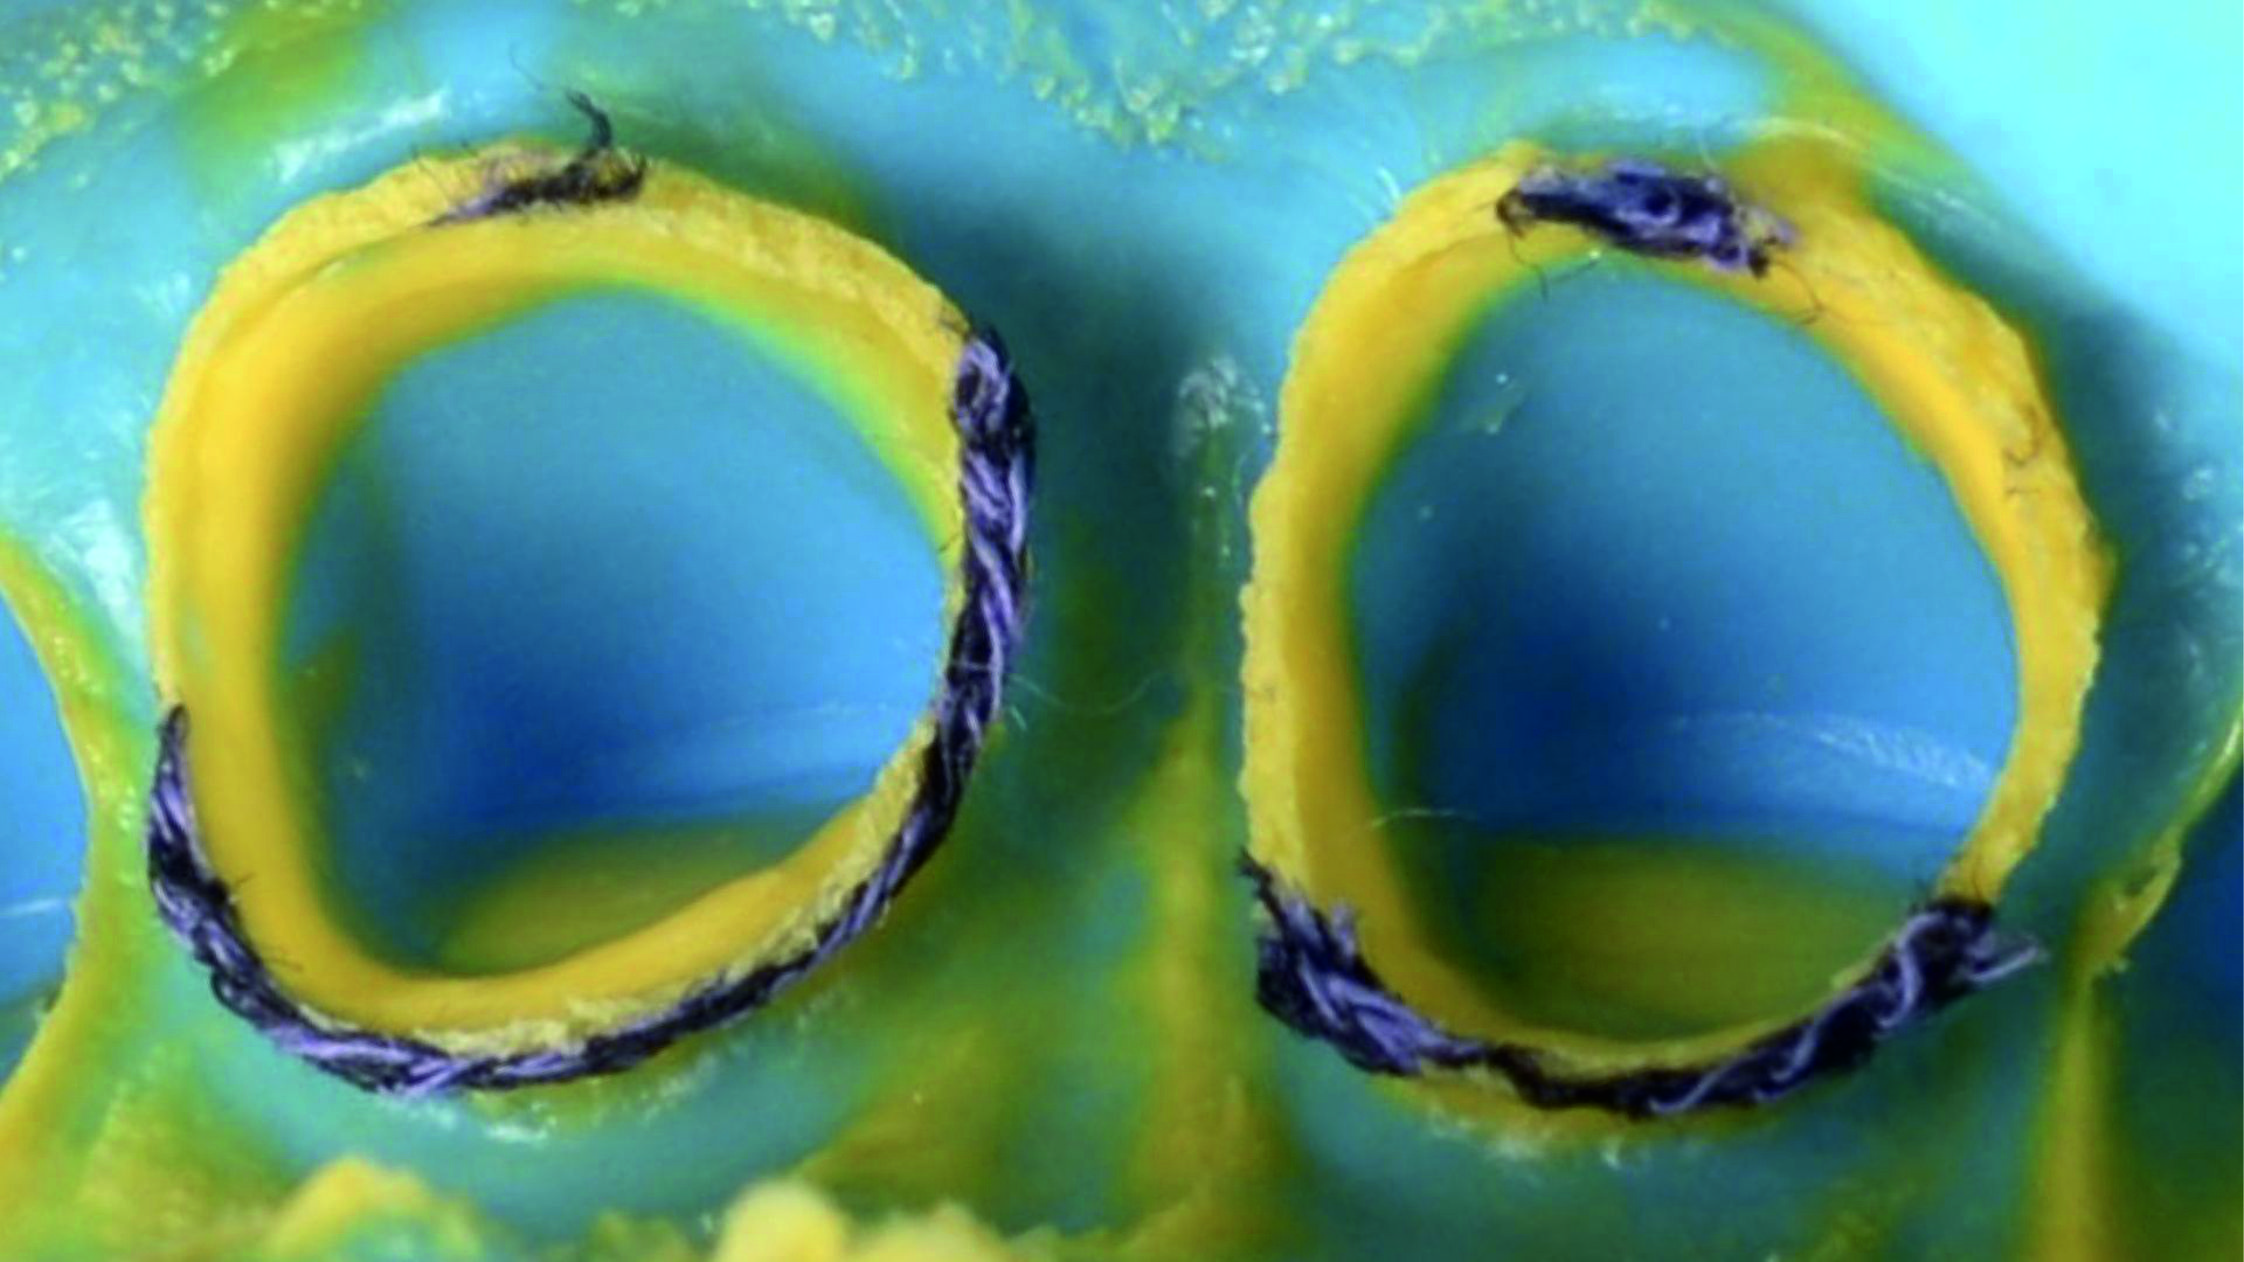

Фото 22. Щоб краще відкрити глибокі краї була використана техніка подвійної нитки. Це означає, що першу ретракційну нитку слід помістити в ясенну борозенку для вертикальної ретракції ясен і залишити там, а другу – частково занурити у борозенку для горизонтальної ретракції та видалити безпосередньо перед зняттям відбитка.

Фото 23. Тут видно, чим відрізняється ретракція ясен із використанням однієї нитки…

Фото 24. … від ретракції після видалення другої нитки.Фото 25. Існує безліч технік, які можна використовувати для передачі даних до лабораторії, але через низку причин найбільш надійною я вважаю одноетапну техніку, яка передбачає одночасне нанесення текучого матеріалу і маси-putty.